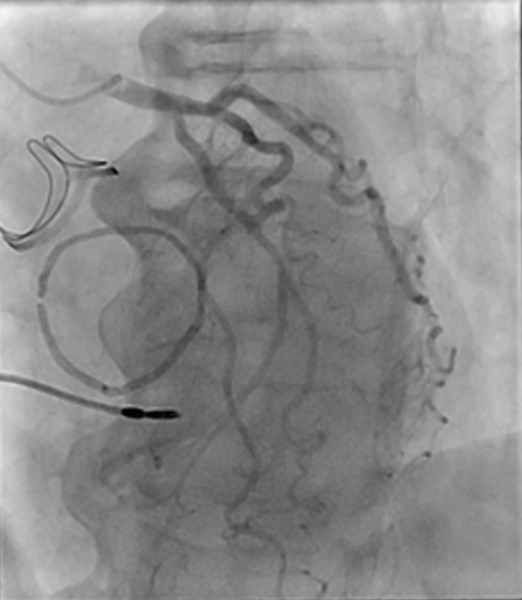

Nouvelle évaluation globale : cathétérisme

- POD : 13 mmHg

- PA 167/70 (100) mmHg

- PAPs 70 mmHg, PAPm 42 mmHg, PAPd 20 mmHg

- Pcap 28 mmHg

- Débit 5,13 L/min

- Index 2,9 L/min/m2

- RVP 2,73 UW

- Stent Circonflexe perméable

- Sténose significative de l’ostium de la bissectrice (traitement médical)